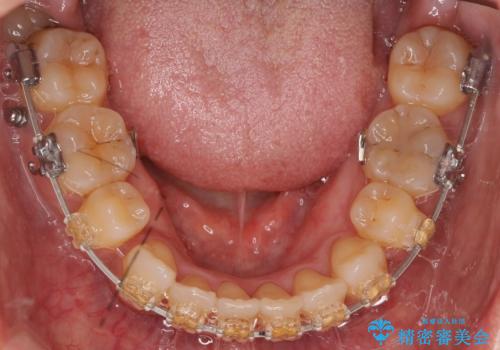

- 矯正装置

- 審美装置

- 前歯の重なりを主訴に来院。

前歯が顔の真ん中に飛び出しているような状態でした。

右上の犬歯が奥深く埋伏していました。

右上以外の3本を抜歯しきちんと並べました。

成人の矯正でしたので、矯正治療前にしっかり必要な歯周病治療を行い、状態が改善してから開始しました。